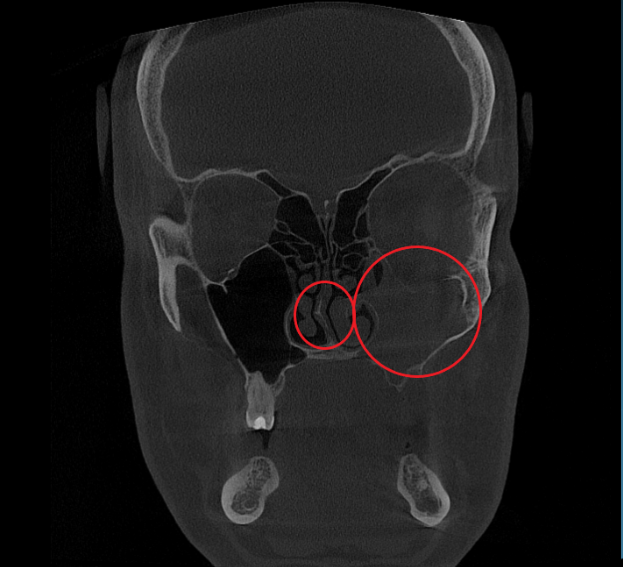

- Компьютерная томография (КЛКТ) околоносовых пазух и височных костей: Этот высокоинформативный метод диагностики объективно показал искривление носовой перегородки вправо, субтотальное снижение пневматизации (воздушности) левой верхнечелюстной пазухи, что свидетельствовало о хроническом воспалительном процессе. Костно-деструктивных изменений не выявлено.

- Хронический левосторонний верхнечелюстной синусит (J32.0). Длительное воспаление слизистой оболочки левой гайморовой пазухи, подтвержденное КТ.